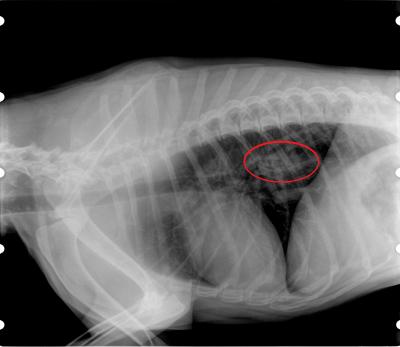

Na RTG snímku vidíme roztažené tlusté střevo plné kostního "cementu" (bílý válcovitý objekt červeně zakroužkovaný).